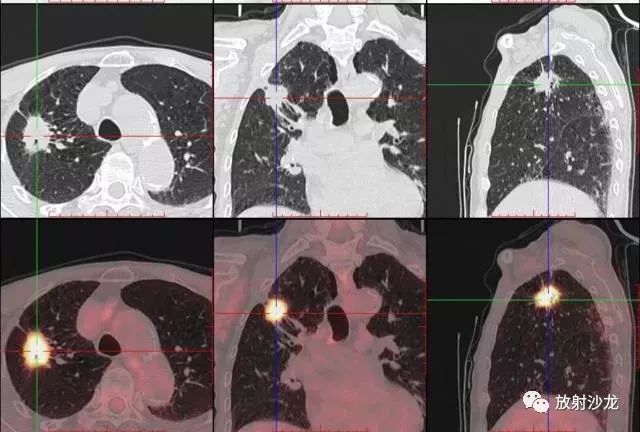

PET-CT是目前世界上最先進(jìn)的核醫(yī)學(xué)分子影像設(shè)備,中文稱為正電子發(fā)射計(jì)算機(jī)斷層/X 線計(jì)算機(jī)體層成像。

PET-CT等于PET+CT,包含PET(功能分子影像)與CT(解剖影像)的最優(yōu)化組合;即同時(shí)具有PET和CT的功能,但它絕不是二者功能的簡(jiǎn)單疊加,因?yàn)镻ET與CT優(yōu)勢(shì)互補(bǔ),“1+1>2”。PET-CT除了具備PET和CT各自的功能外,其獨(dú)有的融合圖像,將PET圖像與CT圖像融合, 可以同時(shí)反映病灶的代謝,可以早期診斷疾病的同時(shí),明顯提高診斷的準(zhǔn)確性。